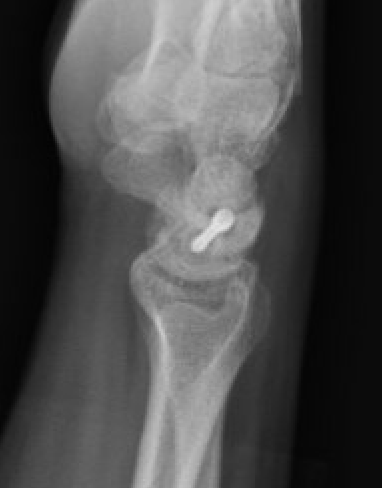

Lateral xray

Increased scapholunate angle > 60o

- scaphoid flexed & lunate extended

- usually 30 - 60o

Scapholunate angle 80o